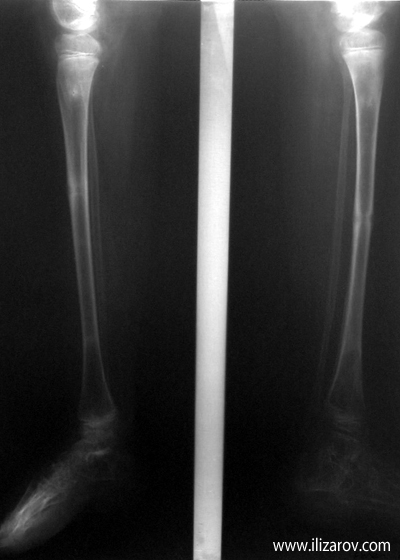

Case 3